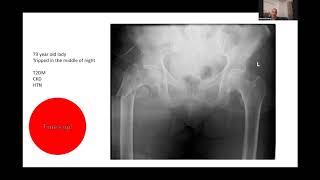

Subtrochanteric Fracture 31A3 - Viva Practice For...

5.665

9:15